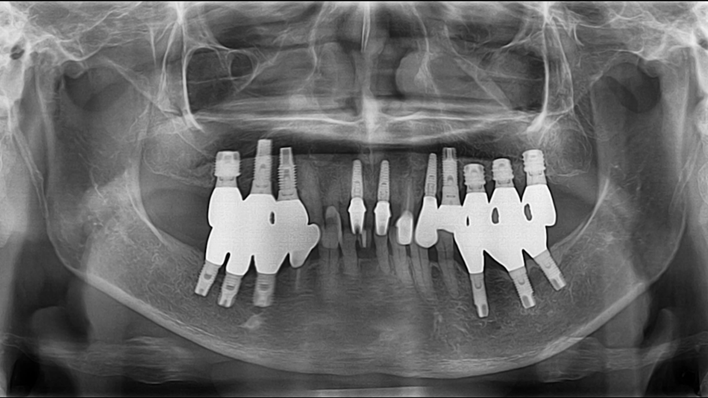

Clinical case: Extraction, immediate placement & loading using

R2GATE solution in aesthetic zone

- Courtesy of Dr. Jong-Cheol Kim, Korea-

Clinical case: : R2GATE guided surgery & immediate implant placement

- Courtesy of Dr. Kwang Bum Park, Korea -